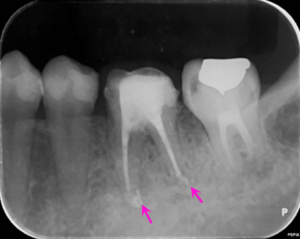

歯の根の中を清掃し終わった後に内部に薬を詰めた直後のレントゲン写真です。

薬は根の中に緊密に詰まっています。一部先から漏れている部分もありますが、のちに吸収されていきます。

根の治療1か月後にグラスファイバーの芯棒を用いた歯の土台(根の治療を行った場合に行う治療です)を立てた際のレントゲン写真です。まだ根の先の骨の溶けている部分の大きさは変わりません。

根の治療2か月後のレントゲン写真です。矢印の部分の骨の溶けている部分の大きさが小さくなっています。